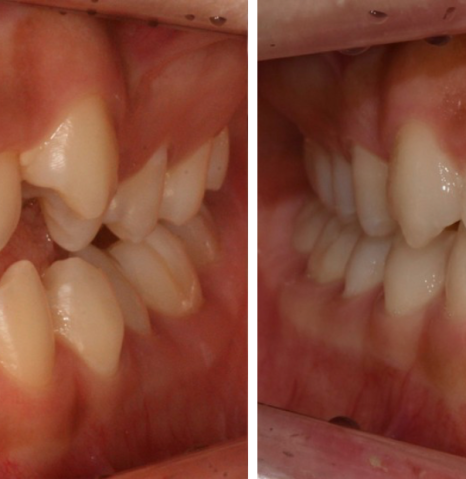

다음은 비발치교정 치료를

진행 한 후 촬영한 모습인데요.

작은 어금니를 발치하지 않은

상태에서 교정을 진행하게 되면,

위 사진에서 표시한 것과 같이

어금니를 포함한 모든 치아를

뒤쪽으로 이동시켜야 하기 때문에

어금니의 교합이나 위치에도

당연히 변화가 발생한다고 했어요.

또한 단순히 영구치를 이동시키는 것만으로

충분한 공간 확보가 어려운 상태인

환자분에게 비발치교정 치료를

적용하게 되면, 오히려 입이 앞으로

돌출되어 보일 수도 있기 때문에

치열 개선에 어려움을 겪는다고 했어요.